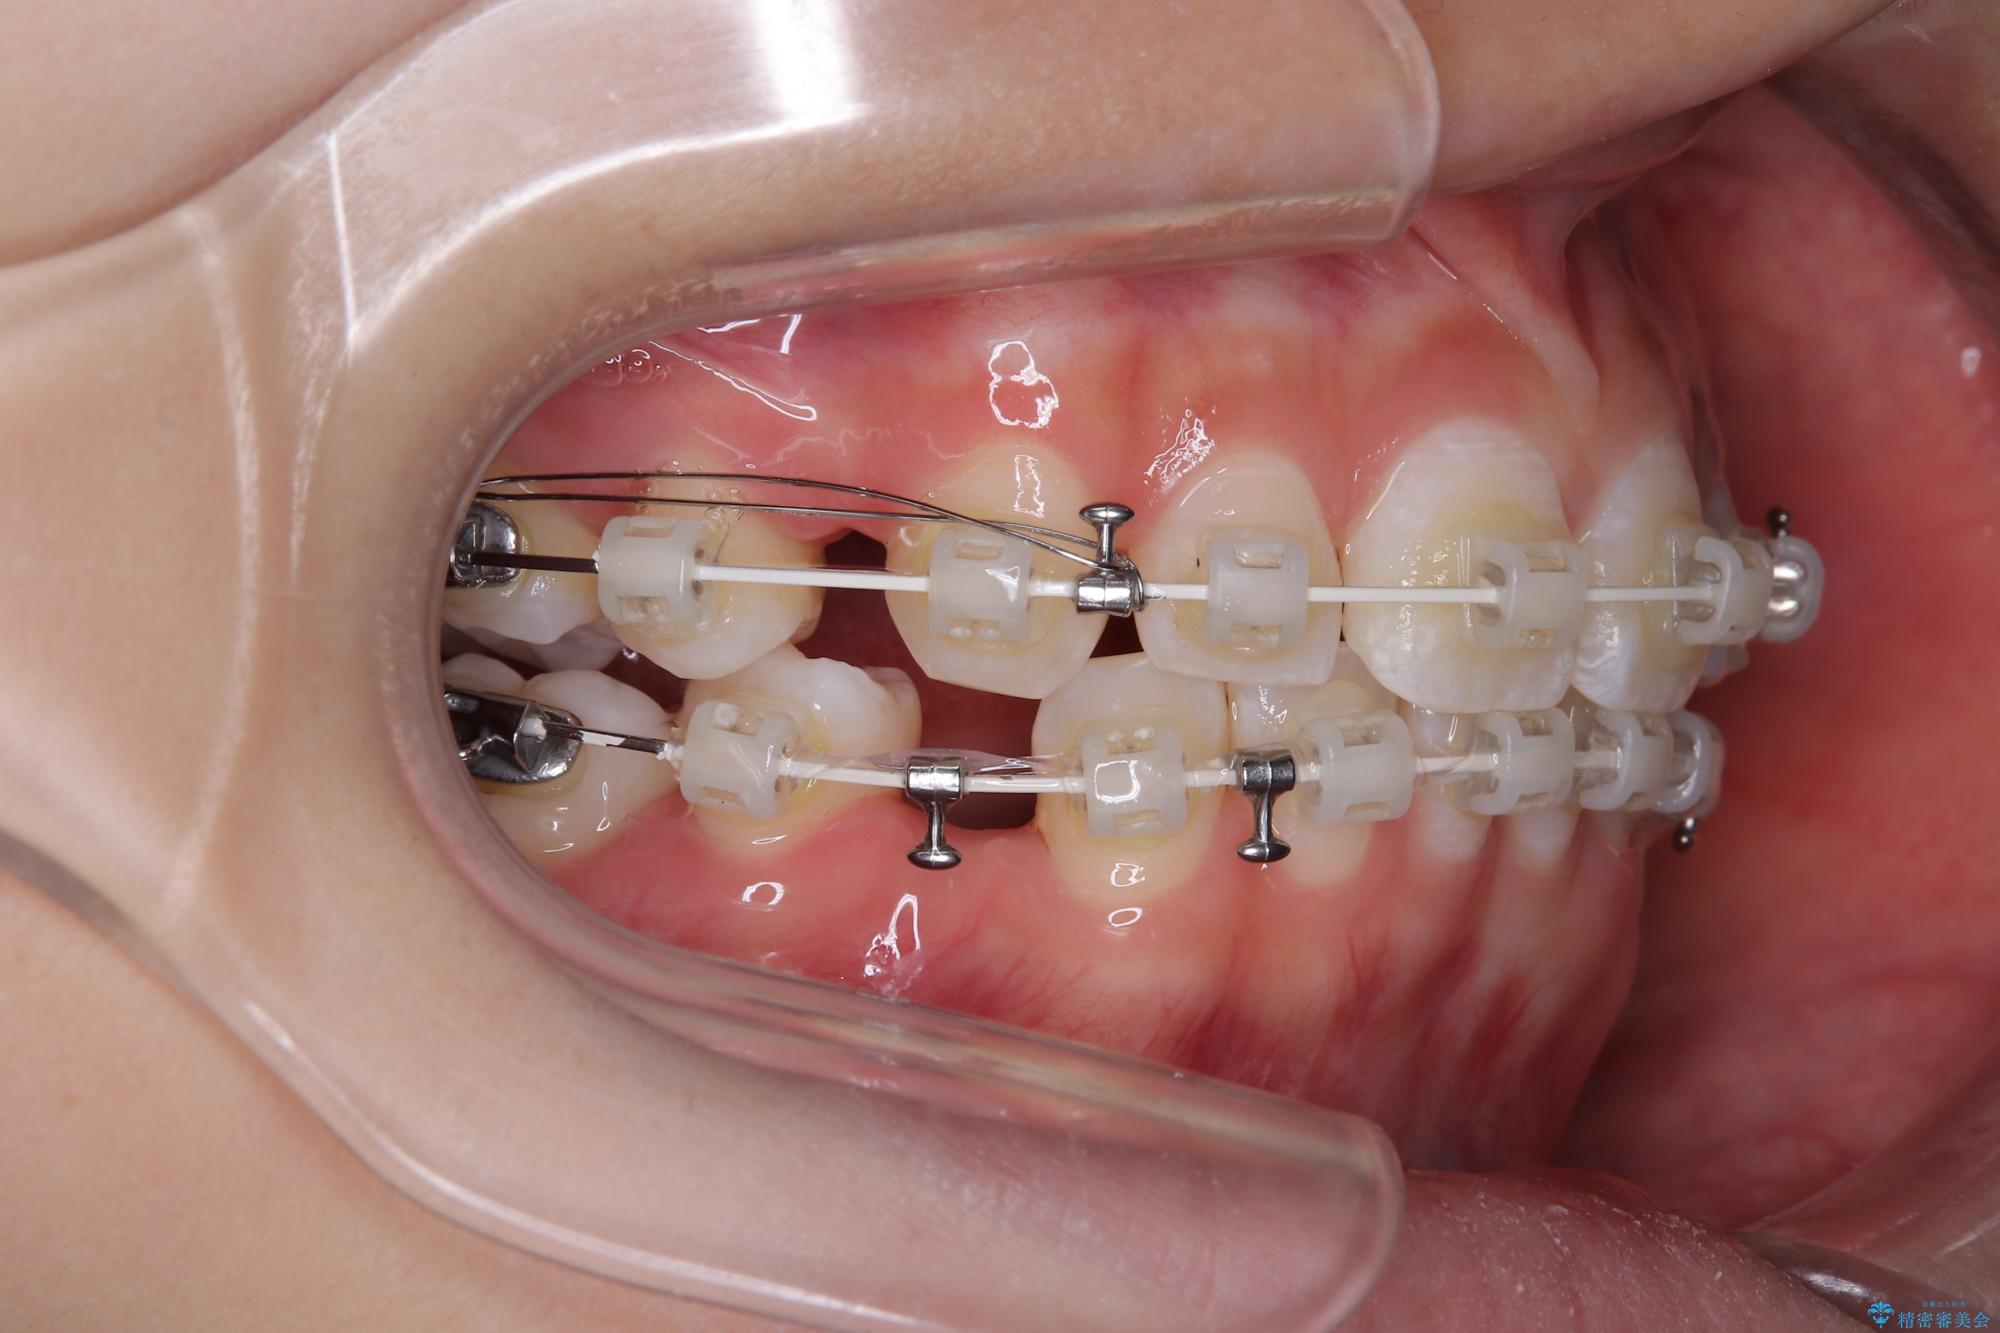

- 矯正装置

- 審美装置

- 2年

- 10-30回

下顎はデコボコが気になっていたため、上下左右第一小臼歯4本を抜去して、ワイヤー装置にて口元の突出感を改善するよう矯正治療を行うこととしました。